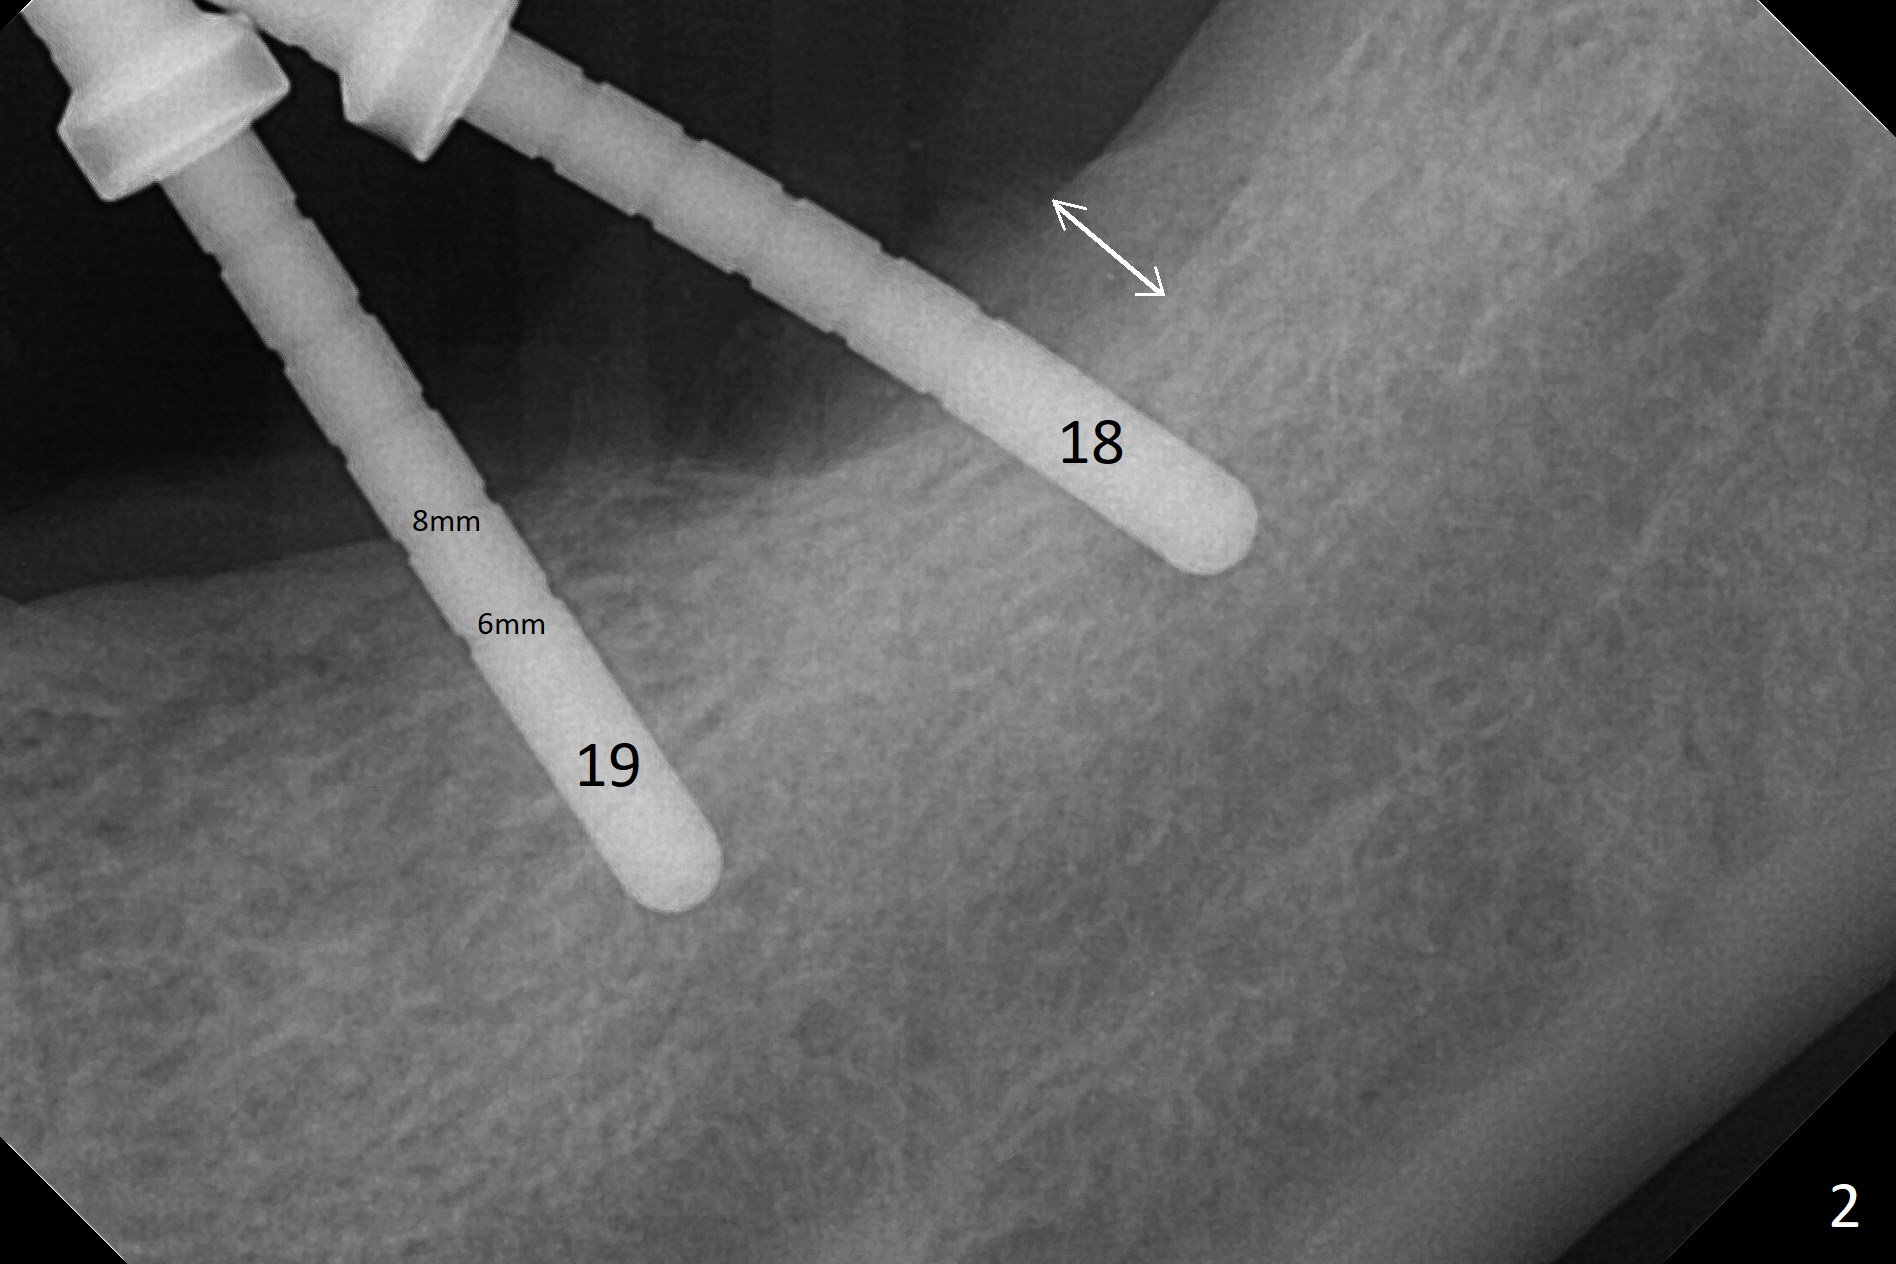

Preop photo shows severe mesial tilt of the tooth #18 (Fig.1). After extraction, the osteotomy is established in the apical end of the socket, where the buccolingual width is limited. It appears that an extra wide implant (5.9 mm) may perforate one of buccolingual plates. On the other hand, the buccal plate (Fig.2 double arrows) is intact and approximately 2 mm tall, whereas the lingual one is thin and lower. Initial osteotomy confirms that bone heights at #18 and 19 are 6 and 8 mm, respectively. Counting 2 mm of the buccal plate and bone graft lingually, a 8 mm long implant may be a practical option at the site of #18. After initial placement of two of 5x8 mm SM implants (Fig.3), the depth of the implant at #19 is adjusted twice (Fig.4,5). With placement of autogenous and allograft (Vanilla, Fig.5 *)) and abutments, a piece of cotton pellet is placed in each abutment well (access, Fig.6 *). Periodontal dressing is applied to the abutment wells for additional retention (Fig.7 *). Due to local poor oral hygiene, splinted provisional is fabricated 4 months postop (Fig.8) in preparation for limited orthodontic uprighting the tooth #20. The patient has pain with mastication at #18 eleven months post cementation (Fig.9). It appears that both of the implants should be removed with immediate replacement and bone graft. Prepare 4 PRF and sticky bone. The new implant will be 5.0 or 5.5x5 mm (Fig.10 green) with 2.3 mm platform (white). A block graft will be harvested from the ipsilateral ramus using 9/8 and 6/5 mm trephine burs for 2-3 mm in depth (Fig.11 blue). The ring graft will be seated around the platform over the implant (Fig.12).